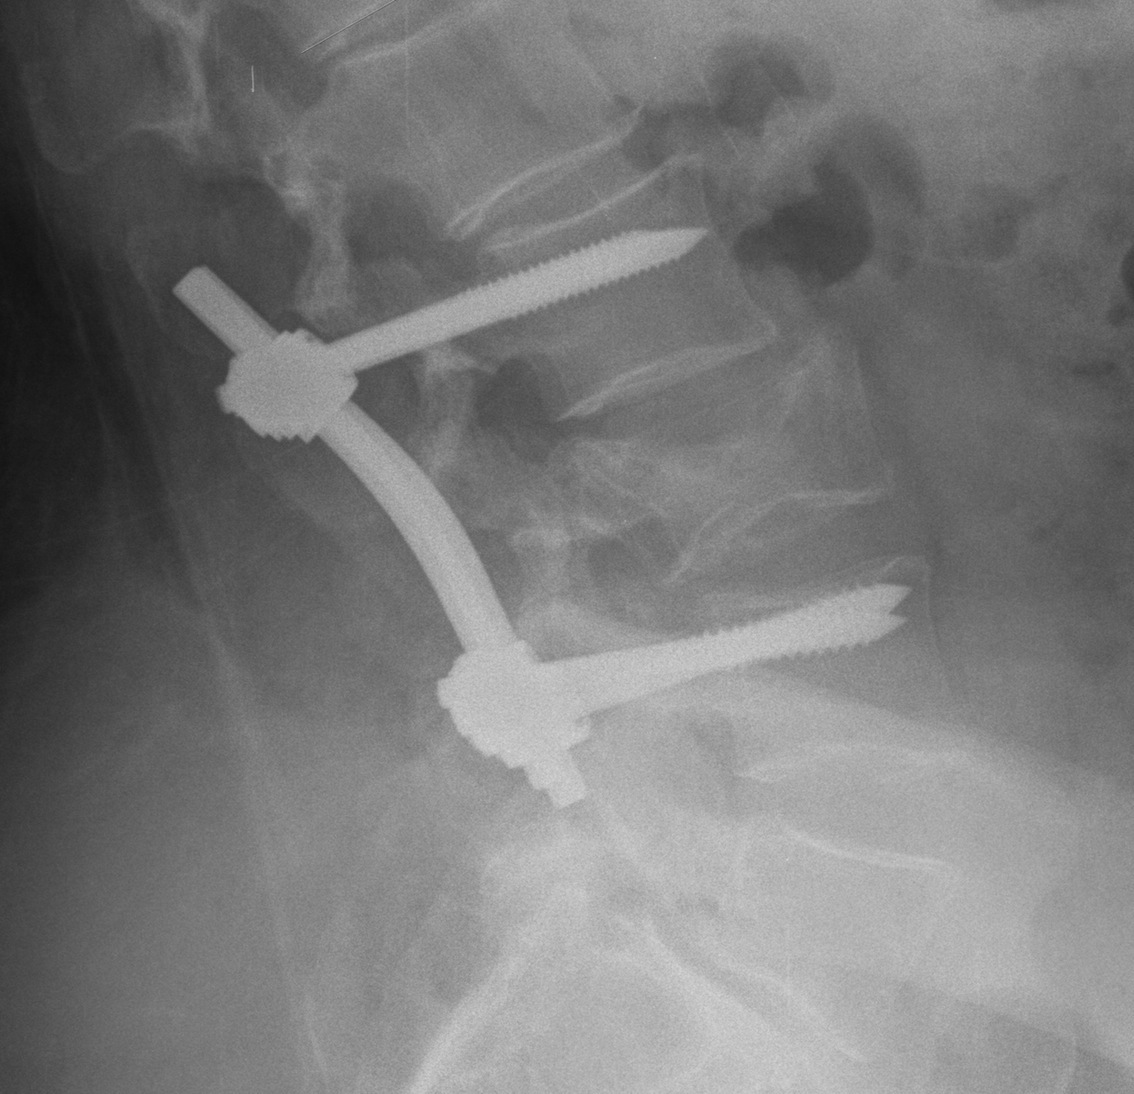

Operative Management

Options

Fusion